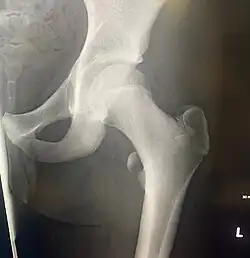

In human anatomy, the lesser trochanter is a conical, posteromedial, bony projection from the shaft of the femur. It serves as the principal insertion site of the iliopsoas muscle.[1]

The lesser trochanter is a conical posteromedial projection of the shaft of the femur, projecting from the posteroinferior aspect of its junction with the femoral neck.[1]

The summit and anterior surface of the lesser trochanter are rough, whereas its posterior surface is smooth.[1]

The intertrochanteric crest (which demarcates the junction of the femoral shaft and neck posteriorly) extends between the lesser trochanter and the greater trochanter on the posterior surface of the femur.[1]